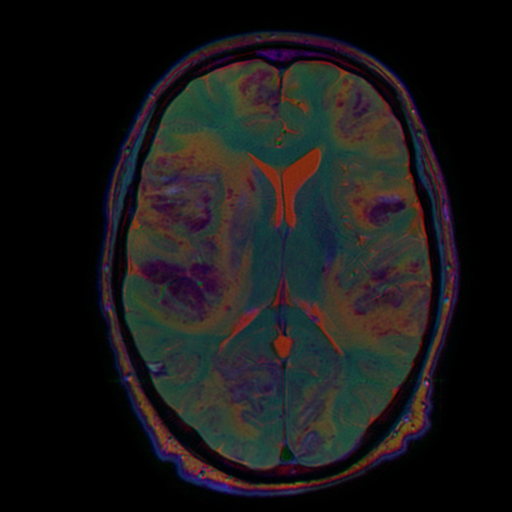

Каждая из этих серий содержит полезную информацию, и мы хотим показывать нейросетке все три взвешенности. Для этого их нужно подавать как каналы (примерно так, как делал фотографии Прокудин-Горский в начале 20 века: делал три фотографии через разные светофильтры, а потом накладывал их друг на друга).

Понятно, что для этого серии должны быть ориентированы идентичным образом. Сейчас покажу, как это можно сделать.

def normalize(data):

%%time

filenamesDICOM = reader.GetGDCMSeriesFileNames('T1_CE')

reader.SetFileNames(filenamesDICOM)

t1_sitk = reader.Execute()

filenamesDICOM = reader.GetGDCMSeriesFileNames('SWI')

swi_sitk = reader.Execute()

filenamesDICOM = reader.GetGDCMSeriesFileNames('T2')

t2_sitk = reader.Execute()

swi_resampled = resample(swi_sitk, t2_sitk)

t1_resampled = resample(t1_sitk, t2_sitk)

t2_sitk_array = normalize(sitk.GetArrayFromImage(t2_sitk))

swi_resampled_array = normalize(sitk.GetArrayFromImage(swi_resampled))

t1_resampled_array = normalize(sitk.GetArrayFromImage(t1_resampled))

stacked = np.stack([t2_sitk_array, swi_resampled_array, t1_resampled_array,])

to_rgb = stacked[:,t2_sitk_array.shape[0]//2,:,:].transpose(1,2,0)

im = Image.fromarray((to_rgb * 255).astype(np.uint8))

im

>>CPU times: total: 5.02 s

Wall time: 3.52 s

final